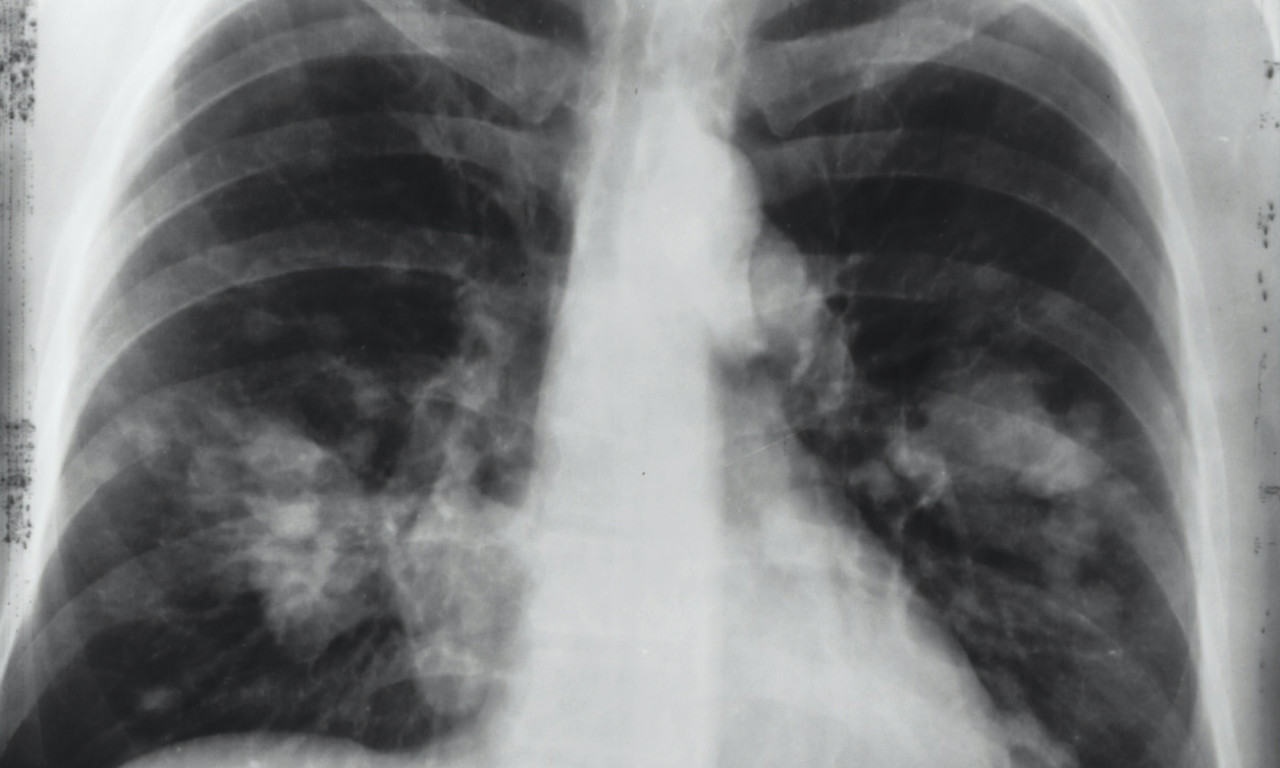

Na svaka dva sata u Srbiji jedna osoba premine od KARCINOMA PLUĆA! Od jeseni počinje "borba" u SRBIJI, a evo i kako

Svetski dan borbe protiv raka pluća obeležava se svake godine 1. avgusta.